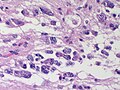

| Glioblastoma, IDH-wildtype (CNS WHO grade 4) | glial processes (esp. on smear), nuclear atypia (typical size var. ~3x, irreg. nuc. membrane, hyperchromasia), no Rosenthal fibres in the core of the lesion †, microvascular proliferation or necrosis | often enhancing (suggests high grade), usu. supratentorial, usu. white matter | usu. old, occ. young | very common, esp. glioblastoma | IDH-1+/-, GFAP+ | |

| Metastasis | sharp interface with brain, often glandular, +/-nucleoli, no glial processes | often cerebellular, well-circumscribed | usu. old | often suspected to have metastatic disease | TTF-1, CK7, CK20, BRST-2 |